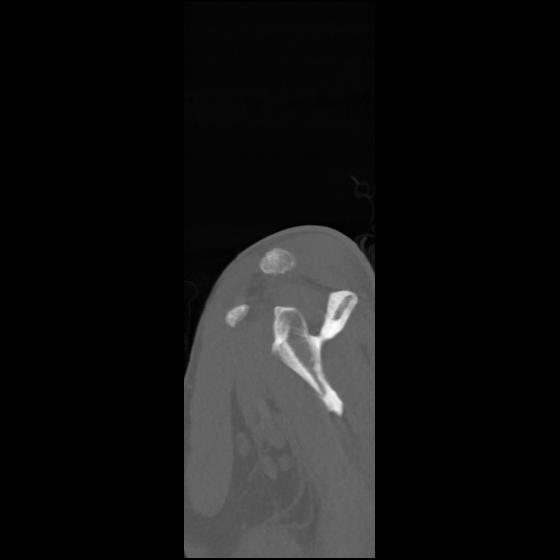

24 ANGIO,CE,Sag-MIP,5.000,ANGIO,Sag-MIP,